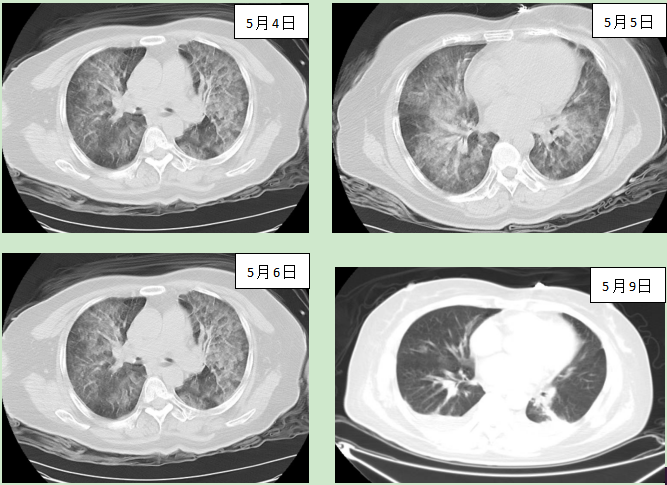

收住ICU后,根据患者的各项指标及CT结果,诊断为“溺水,肺水肿,休克,急性呼吸窘迫综合征”,根据相关评分结果,该患者的死亡风险系数高达83.37%,病情非常危急。

张扬在了解患者病情后,立即组织全科进行病例讨论,制定了详细的诊疗方案。由于患者肺内吸入大量污水,给予高PEEP机械通气,通过体位引流改善肺泡的通气和换气功能,持续泵注升压药稳定患者循环,适当利尿,小剂量激素应用减轻肺水肿,同时保护心、肝、脑、肾等多脏器功能,维持患者水电解质的平衡,防止血栓发生。另外防治肺部感染也是治疗过程中的难点和重点,根据诊疗经验和污水池的环境选择了有效的抗菌药物。

各脏器功能平稳恢复。